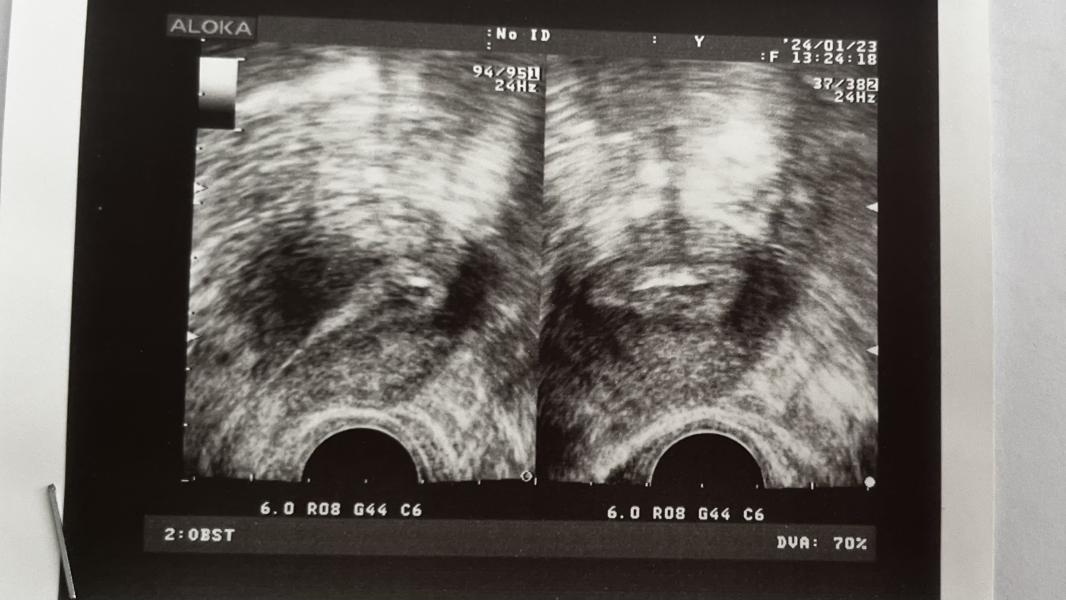

post image